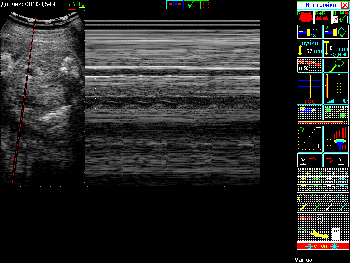

Примеры того, как выглядит экран при различных режимах сканирования можно увидеть в Таблице 4.

Таблица 4. Общий вид экрана в различных режимах сканирования.

Вид экрана Режим сканирования

Режим сканирования B+M Режим В+М